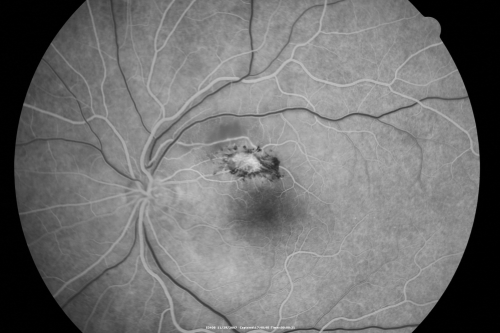

Toxoplasmosis - Inner Retinal - Recurrent - Treated with Bactrim DS

43-year-old man has macular toxoplasmosis. He has responded nicely to Bactrim OS: 20/60